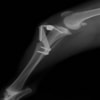

術前左後肢側面像

術後左後肢側面像